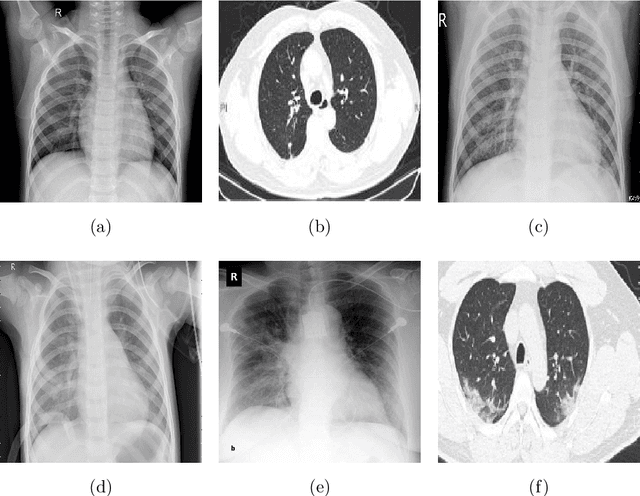

Abstract:The novel Coronavirus Disease 2019 (COVID-19) is a global pandemic disease spreading rapidly around the world. A robust and automatic early recognition of COVID-19, via auxiliary computer-aided diagnostic tools, is essential for disease cure and control. The chest radiography images, such as Computed Tomography (CT) and X-ray, and deep Convolutional Neural Networks (CNNs), can be a significant and useful material for designing such tools. However, designing such an automated tool is challenging as a massive number of manually annotated datasets are not publicly available yet, which is the core requirement of supervised learning systems. In this article, we propose a robust CNN-based network, called CVR-Net (Coronavirus Recognition Network), for the automatic recognition of the coronavirus from CT or X-ray images. The proposed end-to-end CVR-Net is a multi-scale-multi-encoder ensemble model, where we have aggregated the outputs from two different encoders and their different scales to obtain the final prediction probability. We train and test the proposed CVR-Net on three different datasets, where the images have collected from different open-source repositories. We compare our proposed CVR-Net with state-of-the-art methods, which are trained and tested on the same datasets. We split three datasets into five different tasks, where each task has a different number of classes, to evaluate the multi-tasking CVR-Net. Our model achieves an overall F1-score & accuracy of 0.997 & 0.998; 0.963 & 0.964; 0.816 & 0.820; 0.961 & 0.961; and 0.780 & 0.780, respectively, for task-1 to task-5. As the CVR-Net provides promising results on the small datasets, it can be an auspicious computer-aided diagnostic tool for the diagnosis of coronavirus to assist the clinical practitioners and radiologists. Our source codes and model are publicly available at https://github.com/kamruleee51/CVR-Net.